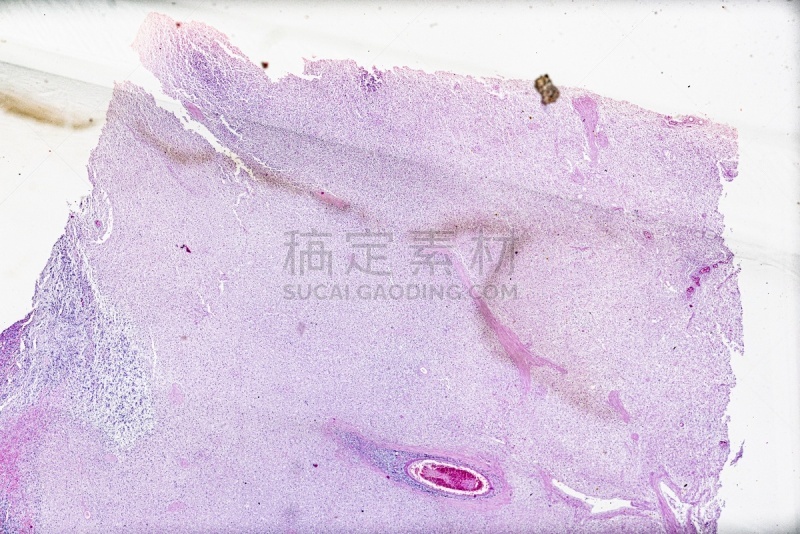

在显微镜下观察肝脏详情